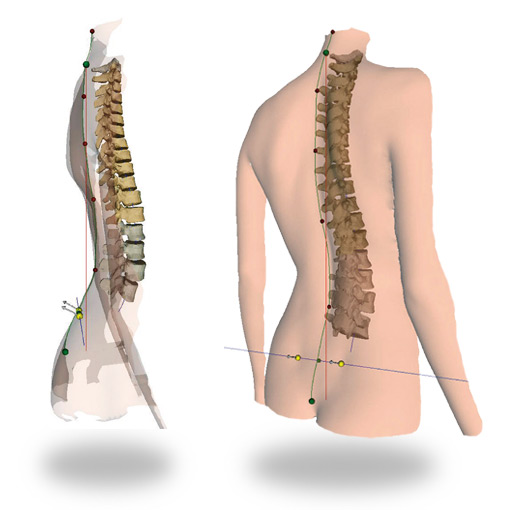

- Система DIERS Formetric 4D (10 кадров) позволяет быстро проводить обследования осанки и позвоночника в статическом режиме. Измерение происходит не инвазивно и без рентгеновского облучения! В результате врач получает большое количество различных клинических параметров для объективного анализа статики тела, осанки, сколиоза и всех форм деформаций позвоночника, и более того система DIERS Formetric 4D строит 3D модель позвоночника пациента.

- С помощью DIERS formetric 4D осуществляется быстрая и точная диагностика заболеваний позвоночника и нарушения осанки. Устройство функционирует по принципу видеорастростереографии. На спину пациента проецируются линии, составляющие сетку. Полученная картина дает возможность сформировать модель спины и позвоночника без использования проникающего излучения. Именно поэтому диагностика и лечение позвоночника с применением прибора DIERS formetric 4D совершенно безопасны для организма человека.

- 3D реконструкция позвоночного стола осуществляется без использования отражающих свет маркеров в качестве ориентиров;

- 3D-Реконструкция поверхности спины и позвоночника без рентгеновского облучения